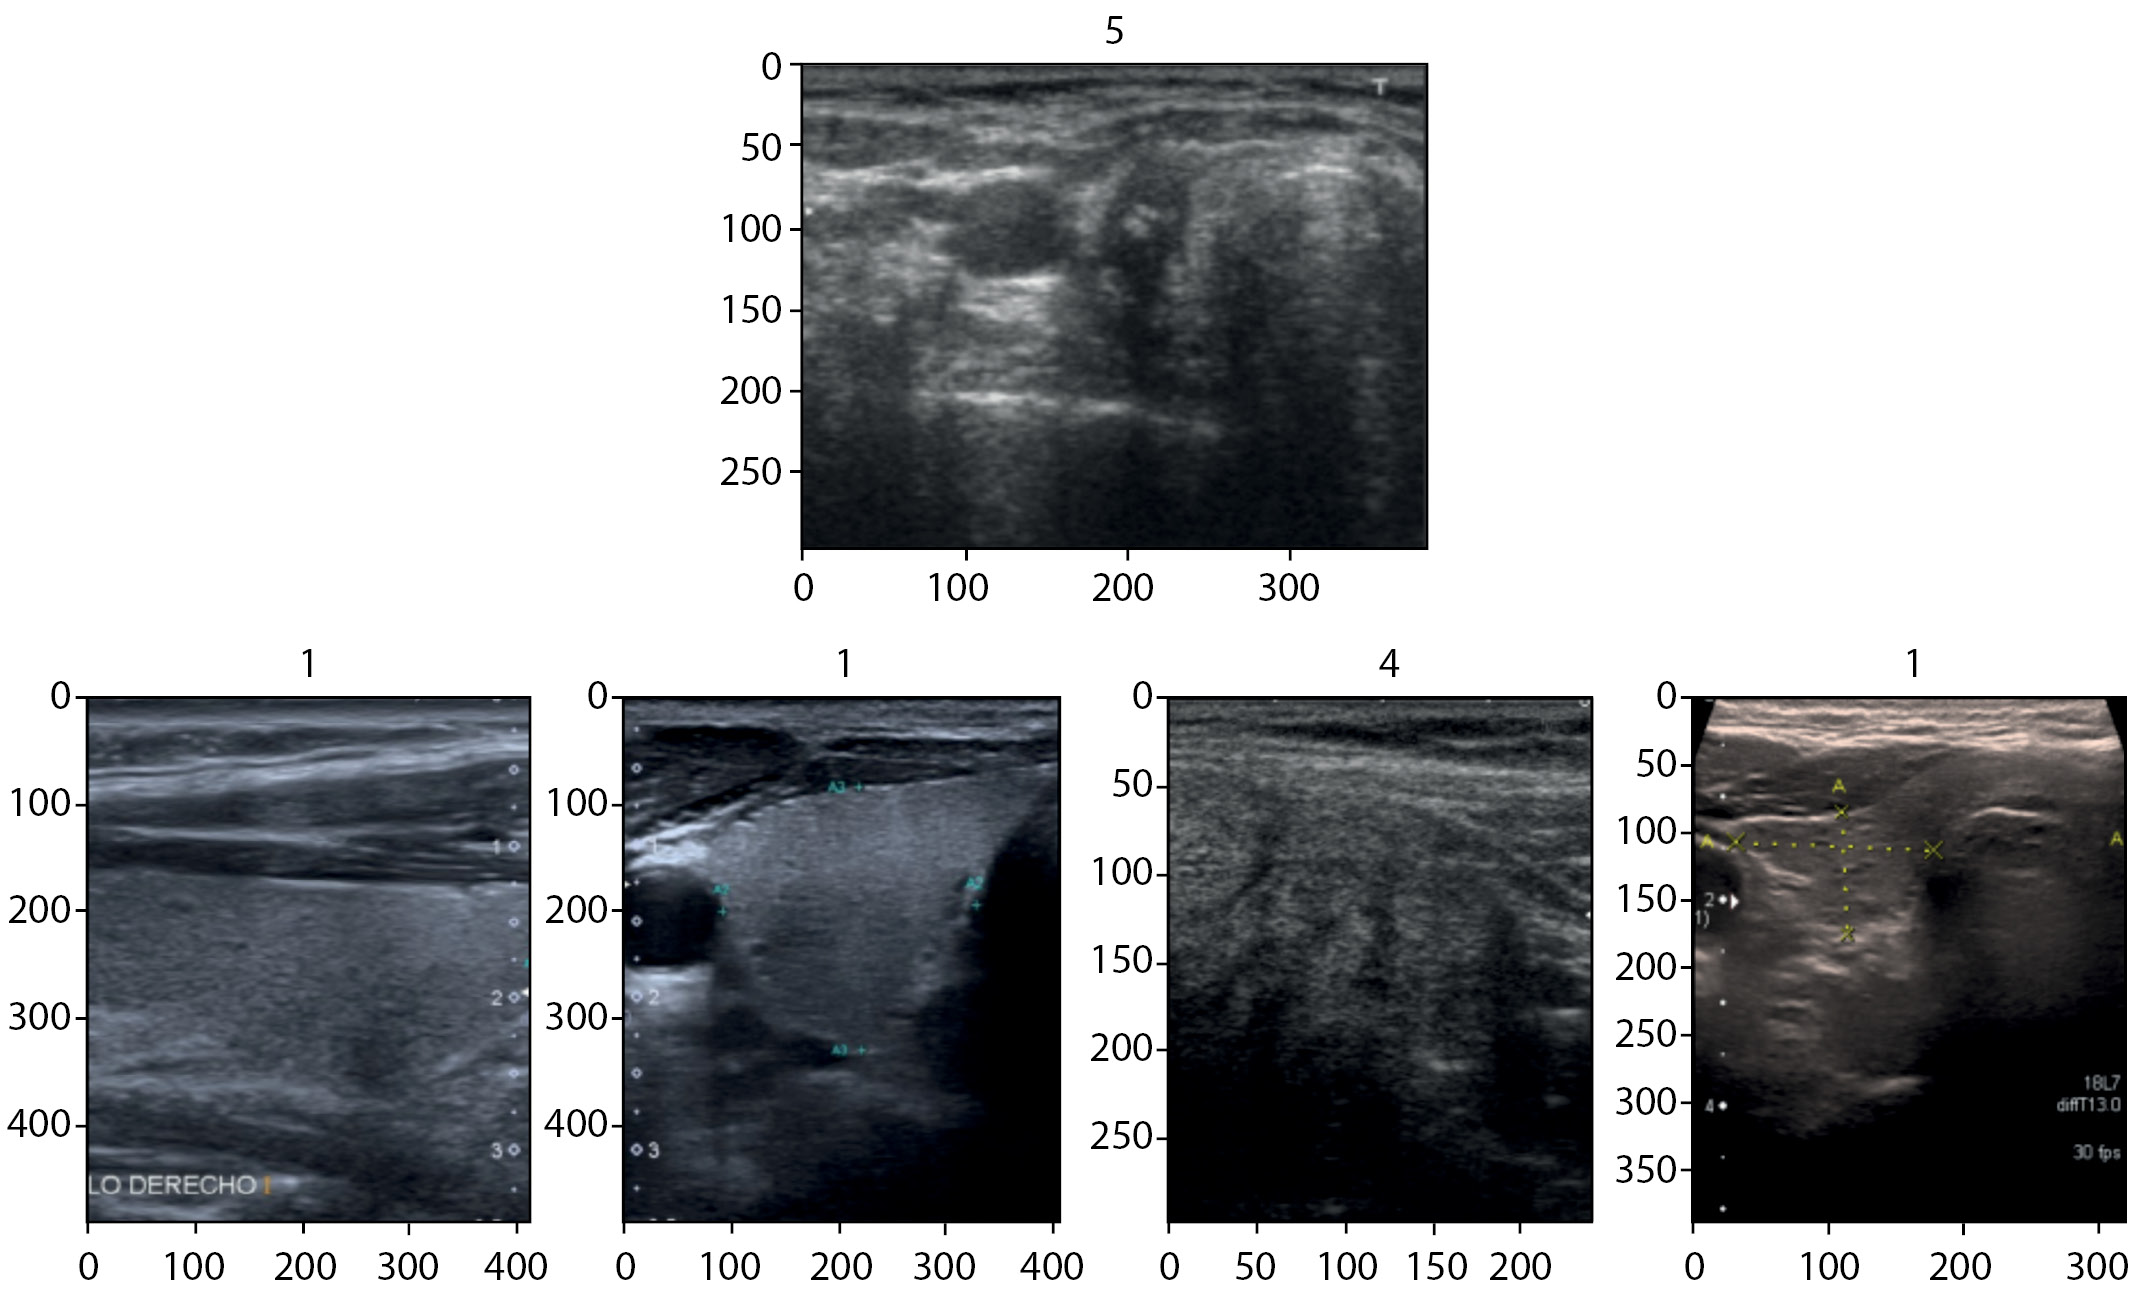

4. Рис. 4. Нормализованные изображения (пример 1, 4, 5 классов). | |